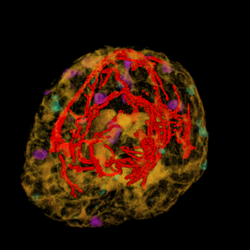

A major task is to implement the abstraction layer for rendering synthetic data, independent of display technology. This may involve use of the MNI's VTk-based IGNS system (IBIS) or build on our own rendering architecture, with low-level rendering engines for each display type, and input taken from existing neuro-visualization tools. In either case, the goal is to integrate the 3D rendering of MRI, fMRI, PET, DTI, and intra-operative ultrasound data, possibly in conjunction with the tracked position of surgical tools, and add modules for additional processing (e.g., feature highlighting, density control, and interactive manipulation/deformation). Rendering strategies must take into account the importance of merging volumetric and surface rendering techniques when dealing with the multiple data sets available.

| cutting plane + MRI | cutting plane + blood vessels | blood vessels + fMRI + PET | blood vessels + fMRI + PET + MRI |